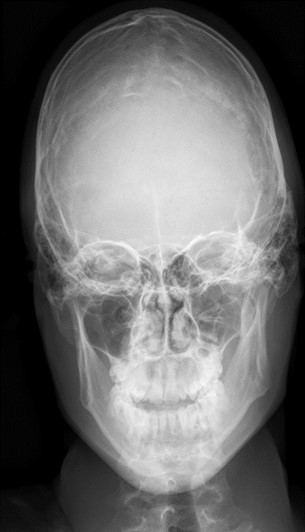

Frontal and lateral skull radiographs revealed generalized cortical thinning as well as a reduction of the orbital spaces (Figure 1).

Figure 1: AP x-ray of the skull shows generalized cortical thinning as well as reduction of the orbital spaces.